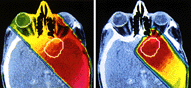

Radiosurgery has been specially helpful

for the localized, highly precise treatment of brain tumors. Due to the

steep fall of the irradiation fields (isodoses) from the center of the

target to be destroyed, the biological inactivation happens only on it;

while the brain, and other vascular and neural structures around it, are

protected. This is achieved through the high mechanical precision of the

radiation source, and the assured reproducibility of the target. The precision

in the positioning of the patient, in the calculation of dosages, and in

the safety of the patient, are all extremely high.

Radiosurgery is indicated primarily for the therapy of tumors of the brain and of the hypophysis. These tumors can be primary (i.e., they originated in the brain tissue itself) or metastatical (i.e., they originated from the spread of primary tumors growing in other parts of the body). Radiosurgery works equally well with benign or malignant tumors. |

| The effect of a stereotactic radiosurgery

on a brain tumor Left: before surgery. Right: 4 months after surgery |